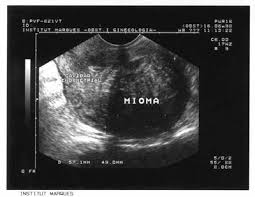

La terapia de ultrasonidos se consolida como alternativa a la cirugía en el tratamiento de miomas uterinos

Esta técnica no requiere anestesia ni hospitalización y no deja cicatrices ni secuelas físicas en la mujer, lo que permite su incorporación a la rutina de forma prácticamente inmediata.

Los ultrasonidos focalizados de alta intensidad (high-intensity focused ultrasound) se han consolidado como alternativa a la cirugía en el tratamiento de miomas uterinos no invasivos, con un grado de éxito de hasta el 90%. Desde que se comenzó a aplicar en 2008, la prescripción de HIFU se ha incrementado en un 80%, en proporción inversa a la del resto de terapias, convirtiéndose en el tratamiento de referencia de Myoma Institute para esta patología, de modo que actualmente el 70% de los casos son tratados mediante HIFU.

Las ondas de ultrasonidos se dirigen hacia el tejido a tratar mediante el transductor HIFU, provocando en el punto focal un incremento de la temperatura de los tejidos (a 65-100º) que causa necrosis coagulativa en un área de 2-3 mm, hasta destruir las células del mioma. Estas ondas viajan a través de los tejidos adyacentes sin dañarlos. A diferencia de otras técnicas similares de ultrasonidos, en la utilizada por Myoma Institute las ondas son guiadas mediante monitorización en tiempo real por ecografía, lo que permite la evaluación y control inmediato de los cambios producidos en el tejido enfermo, repercutiendo en una mayor precisión del tratamiento y seguridad para la paciente.